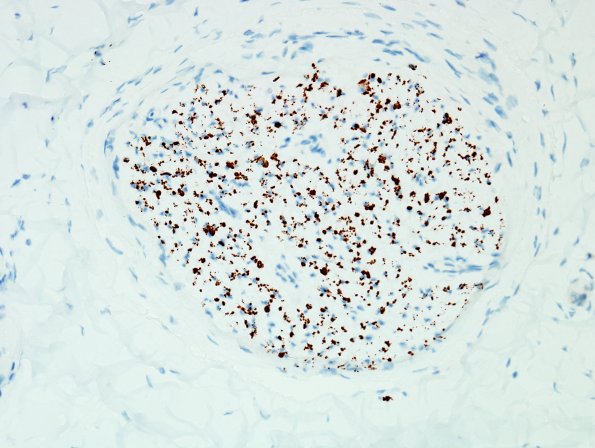

9B2 CIDP, (Case 9) compare with H&E NF 40X.jpg

However, there are numerous axons remaining in all of the fascicles, suggesting demyelination. (NF IHC)